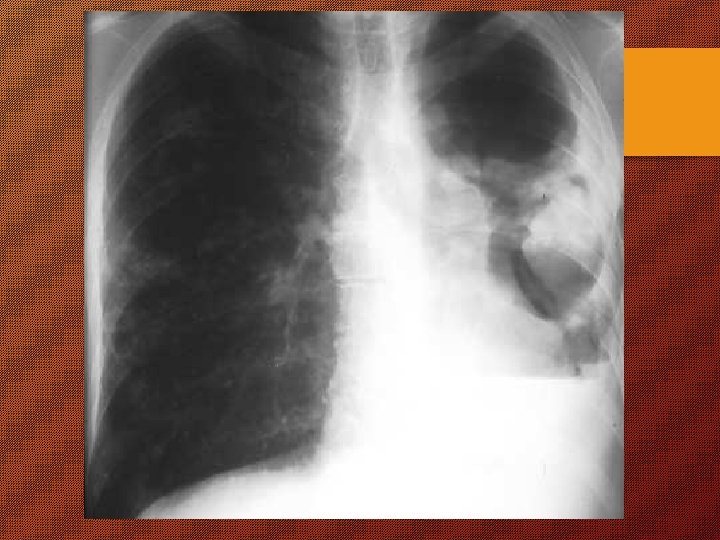

KAPAN DIPIKIRKAN SESEORANG MENDERITA TB ? Ø “batuk berdahak terus menerus 2 minggu atau lebih” (3 B) batuk darah atau dahak bercampur darah Ø Ø lemas, nyeri dada nafsu makan kurang Ø Ø Ø sesak nafas BB menurun demam meriang > 1 bln berkeringat malam tanpa kegiatan fisik.

Suspek TB (tersangka TB) “batuk berdahak terus menerus 2 minggu atau lebih”

Pemeriksaan Pasien TB Ø harus diperiksa dahaknya dgn menggunakan mikroskop Ø pemeriksaan lain sebagai tambahan. Pemeriksaan dahak untuk : - diagnosis - menilai kemajuan pengobatan - menentukan potensi penularan (positif 1 - 2 - 3).